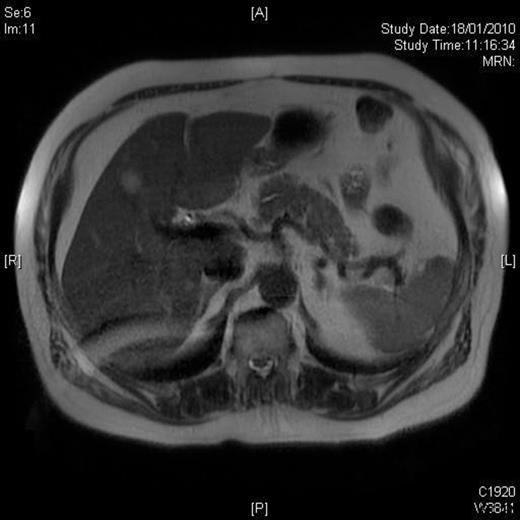

A 58-year-old Caucasian man presented with chest pain, on a background of type-II diabetes mellitus, hypertension and hypercholesterolaemia. A Cardiologist excluded ischaemic heart disease. Full blood count was normal, and an ultrasound scan of the abdomen revealed a 5.5-cm splenic lesion. Computed tomography (CT) revealed a 55mm X 36mm hypodense lesion in the upper pole of the spleen, while magnetic resonance imaging (MRI) demonstrated a well-circumscribed exophytic round mass arising from the anterior aspect of the spleen with features compatible with a benign solid tumour of uncertain malignant potential and multiple liver haemangiomas [Figures 1 and 2]. We proceeded to LPS after the patient had received preoperative vaccinations lest total splenectomy might be necessary.

T1W post-gadolinium MRI: the mass demonstrates a degree of late enhancement